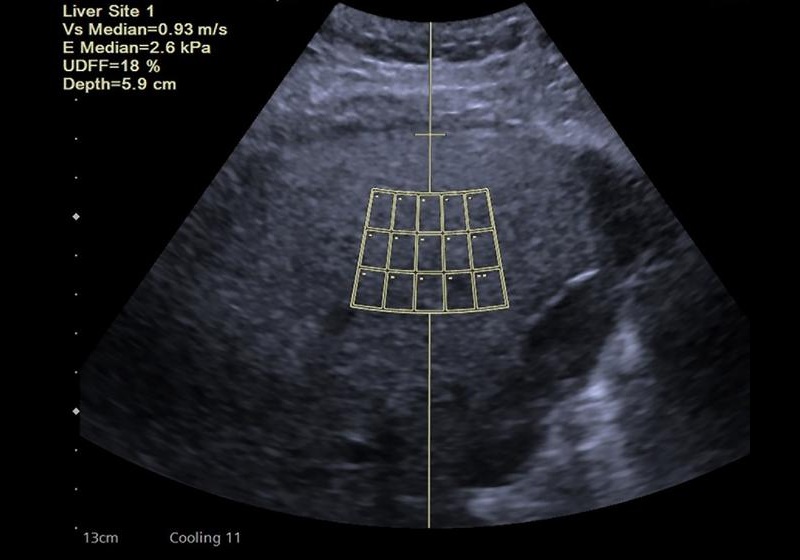

- Focused Ultrasound Shows Effective Against Glioblastoma